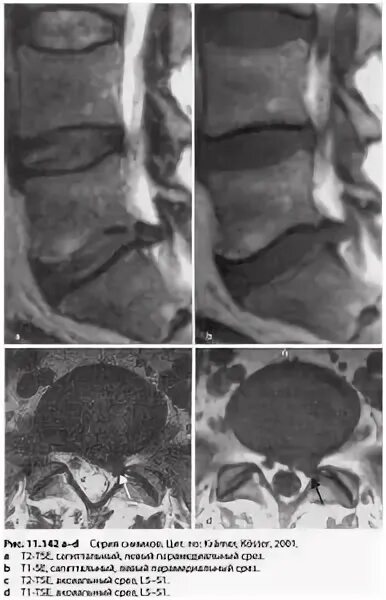

Деформация дурального мешка поясничного